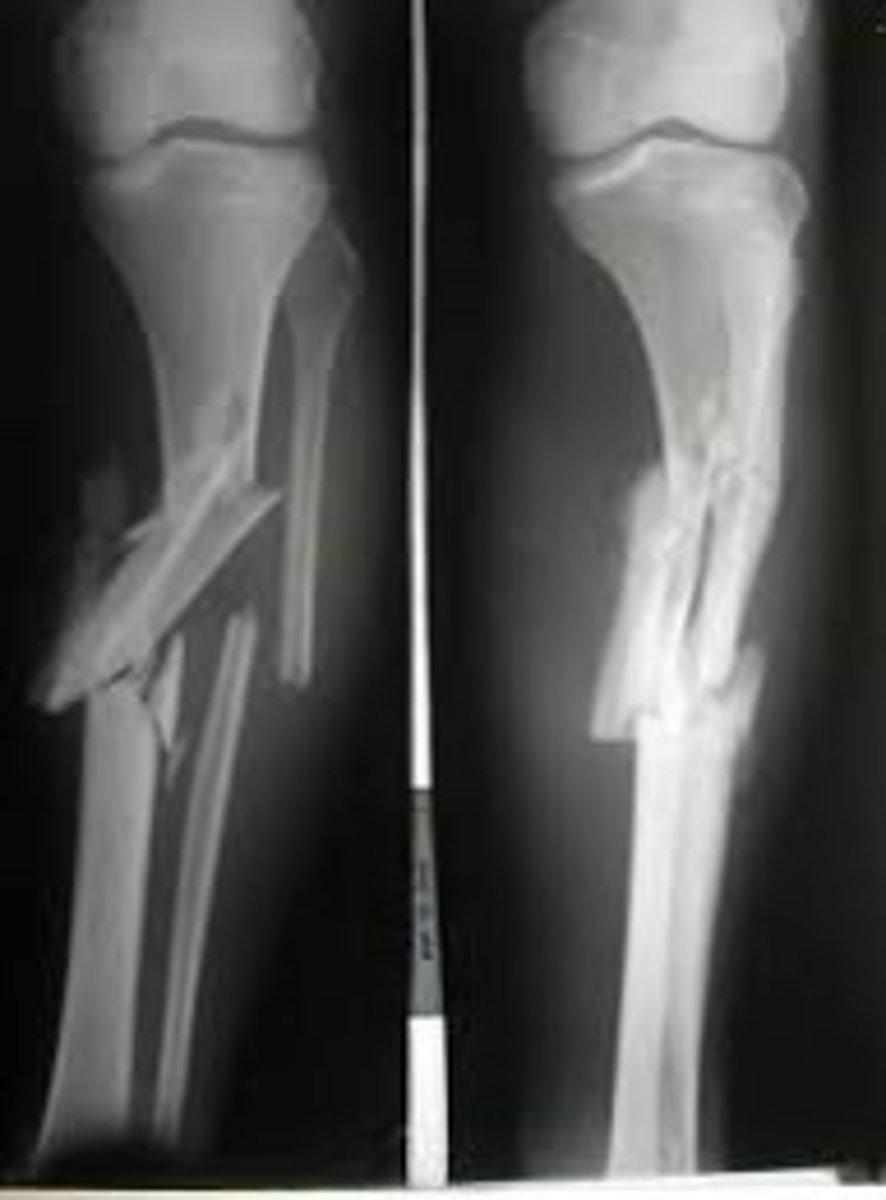

Fracture of proximal half of ulna with dislocation of radial head

Monteggia fx